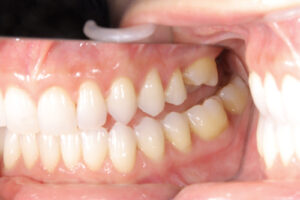

左上第一大臼歯がありません。そのせいか矯正中に第二大臼歯が近心に傾いています。

そのため第二大臼歯近心の下は歯磨きができません。そのため歯が染みています。